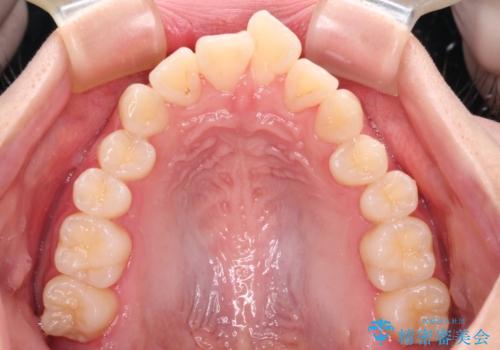

- 前歯がくちばしのように飛び出していることを気にして来院された患者様です。

唇が前方に突出している横顔が気になっているため、上下左右の第一小臼歯4本を抜歯し、ワイヤー装置にて矯正治療を行うこととしました。